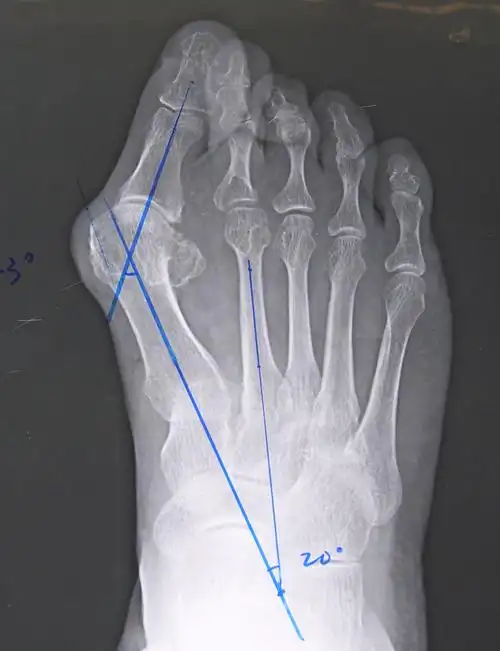

俗称"大脚骨",现行右足矫形,软组织,籽骨松解复位 chevron截骨 关节囊